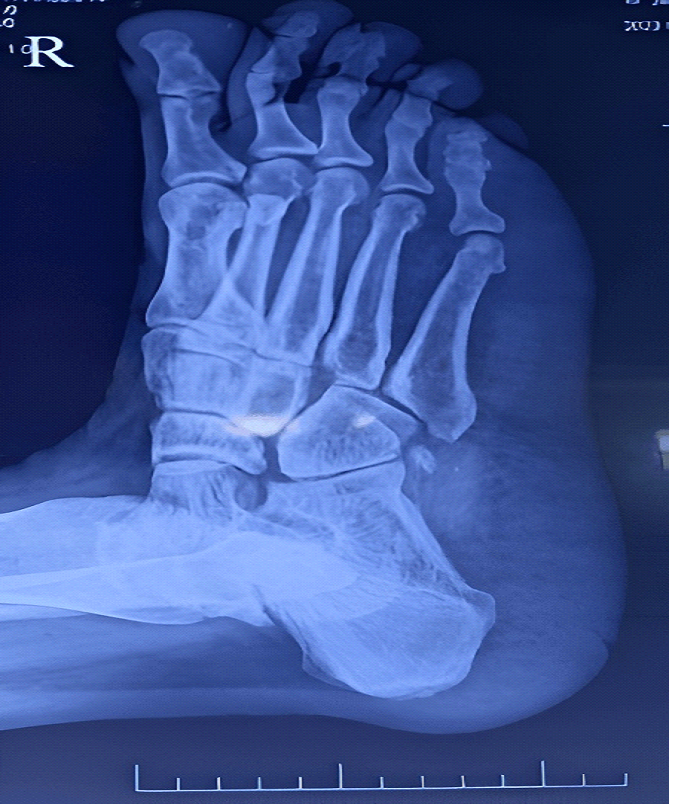

reflex in the left lower limb. A non-contrast CT (Computed Tomography) scan of

the brain revealed an acute infarct in the right middle cerebral artery (MCA)

territory. X- ray foot of the patient showed increased heel pad thickness,

suggestive of acromegaly (Figure 1). Routine blood tests show results

within the normal range (Table 1).

Figure 1: X-ray foot of the patient showing increased heel

pad thickness suggestive of acromegaly